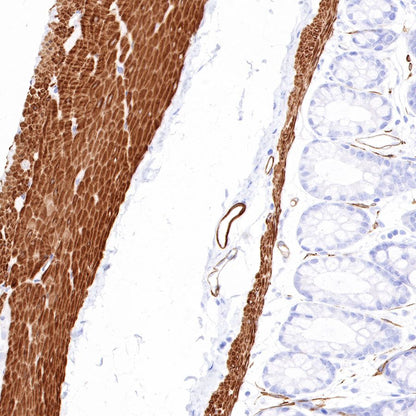

IHC shows positive staining in paraffin-embedded human colon. Anti-Smooth Muscle Myosin Heavy Chain (SMMHC) antibody was used at 1/1000 dilution, followed by a HRP Polymer for Mouse & Rabbit IgG (ready to use). Counterstained with hematoxylin. Heat mediated antigen retrieval with Tris/EDTA buffer pH9.0 was performed before commencing with IHC staining protocol.

IHC shows positive staining in paraffin-embedded human stomach. Anti-Smooth Muscle Myosin Heavy Chain (SMMHC) antibody was used at 1/1000 dilution, followed by a HRP Polymer for Mouse & Rabbit IgG (ready to use). Counterstained with hematoxylin. Heat mediated antigen retrieval with Tris/EDTA buffer pH9.0 was performed before commencing with IHC staining protocol.

IHC shows positive staining in paraffin-embedded human prostatic hyperplasia. Anti-Smooth Muscle Myosin Heavy Chain (SMMHC) antibody was used at 1/1000 dilution, followed by a HRP Polymer for Mouse & Rabbit IgG (ready to use). Counterstained with hematoxylin. Heat mediated antigen retrieval with Tris/EDTA buffer pH9.0 was performed before commencing with IHC staining protocol.

Negative control: IHC shows negative staining in paraffin-embedded human skeletal muscle. Anti-Smooth Muscle Myosin Heavy Chain (SMMHC) antibody was used at 1/1000 dilution, followed by a HRP Polymer for Mouse & Rabbit IgG (ready to use). Counterstained with hematoxylin. Heat mediated antigen retrieval with Tris/EDTA buffer pH9.0 was performed before commencing with IHC staining protocol.

IHC shows positive staining in paraffin-embedded mouse stomach. Anti-Smooth Muscle Myosin Heavy Chain (SMMHC) antibody was used at 1/1000 dilution, followed by a HRP Polymer for Mouse & Rabbit IgG (ready to use). Counterstained with hematoxylin. Heat mediated antigen retrieval with Tris/EDTA buffer pH9.0 was performed before commencing with IHC staining protocol.

IHC shows positive staining in paraffin-embedded rat colon. Anti-Smooth Muscle Myosin Heavy Chain (SMMHC) antibody was used at 1/1000 dilution, followed by a HRP Polymer for Mouse & Rabbit IgG (ready to use). Counterstained with hematoxylin. Heat mediated antigen retrieval with Tris/EDTA buffer pH9.0 was performed before commencing with IHC staining protocol.